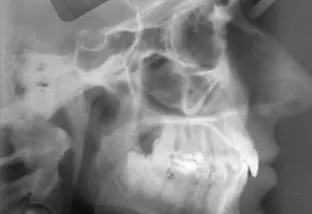

Radiologia

La teleradiografia è una radiografia da cui si ottiene un'immagine...